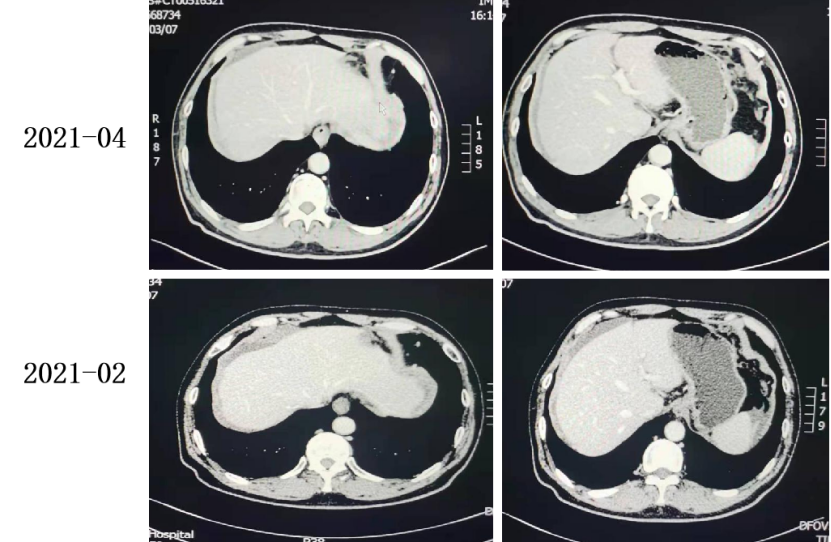

2021-04至2021-05 TAS-102+贝伐珠单抗。

复查CT:腹膜增厚,提示腹膜转移,较前变化不大。

2021-06至今 TAS-102+贝伐珠单抗。